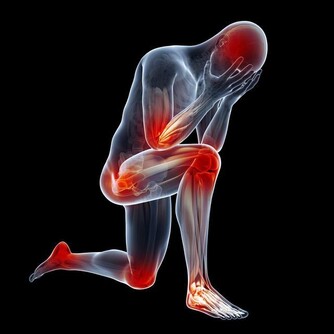

2. 神經根型:是指椎間盤突出或者骨贅壓到了神經根,症狀一般為頸部疼痛,手指麻木、皮膚感覺能力減退,嚴重者還可出現手的大小魚際和骨間肌萎縮。

由上可知,頸椎病的表現形式可以多種多樣,小的突出或骨贅可能只壓迫一種組織,臨床出現症狀也少,大的骨贅可以壓迫多個組織,臨床表現也複雜。如初期為頸肩臂疼痛等神經根症狀,數年後出現頭暈、耳鳴等椎動脈或交感神經受累症狀。

很多人覺得頸椎病是小病,但是如果頸椎病嚴重的話,壓迫到交感神經影響到心臟,可以出現頸源性心髒病,出現心絞痛;壓迫到椎動脈,可能會急轉項時,引發忽然暈倒;壓迫到脊髓,猛地跌倒可能會造成脊髓的損傷,出現肢體癱瘓。這些都是可能的潛在危害。